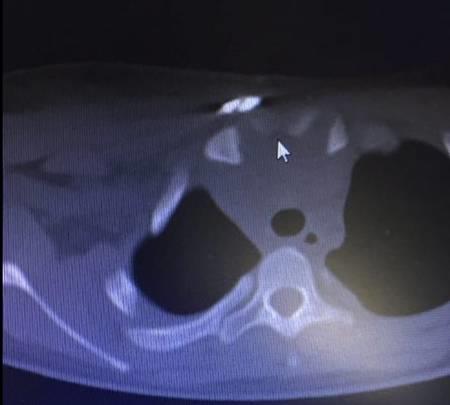

▲术后CT显示右胸锁关节复位固定良好

▲CT断层显示手术复位后上纵膈压迫解除

由于锁骨胸骨端向胸骨后严重移位达3cm,医务人员3次尝试牵引未能成功后,并没有放弃,再次小心翼翼的加大牵引,这时只听见“哗”的一声,锁骨胸骨端成功牵出。

来不及喘上一口气,王荣诗、黄云立即探查伤口深处是否存在大出血迹象,经探查,未出现大出血情况,手术顺利完成。